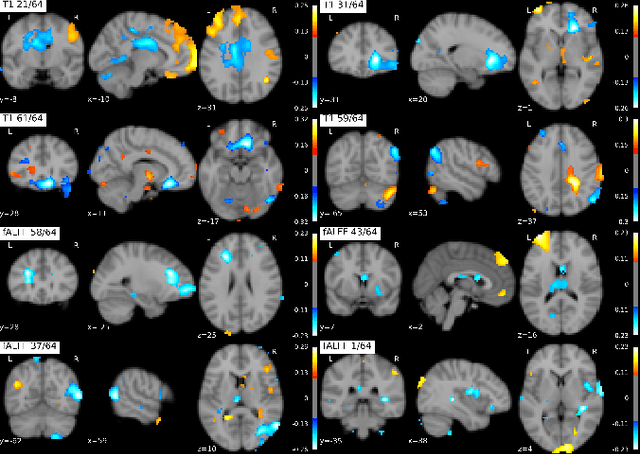

Abstract:Recent neuroimaging studies that focus on predicting brain disorders via modern machine learning approaches commonly include a single modality and rely on supervised over-parameterized models.However, a single modality provides only a limited view of the highly complex brain. Critically, supervised models in clinical settings lack accurate diagnostic labels for training. Coarse labels do not capture the long-tailed spectrum of brain disorder phenotypes, which leads to a loss of generalizability of the model that makes them less useful in diagnostic settings. This work presents a novel multi-scale coordinated framework for learning multiple representations from multimodal neuroimaging data. We propose a general taxonomy of informative inductive biases to capture unique and joint information in multimodal self-supervised fusion. The taxonomy forms a family of decoder-free models with reduced computational complexity and a propensity to capture multi-scale relationships between local and global representations of the multimodal inputs. We conduct a comprehensive evaluation of the taxonomy using functional and structural magnetic resonance imaging (MRI) data across a spectrum of Alzheimer's disease phenotypes and show that self-supervised models reveal disorder-relevant brain regions and multimodal links without access to the labels during pre-training. The proposed multimodal self-supervised learning yields representations with improved classification performance for both modalities. The concomitant rich and flexible unsupervised deep learning framework captures complex multimodal relationships and provides predictive performance that meets or exceeds that of a more narrow supervised classification analysis. We present elaborate quantitative evidence of how this framework can significantly advance our search for missing links in complex brain disorders.

Abstract:Introspection of deep supervised predictive models trained on functional and structural brain imaging may uncover novel markers of Alzheimer's disease (AD). However, supervised training is prone to learning from spurious features (shortcut learning) impairing its value in the discovery process. Deep unsupervised and, recently, contrastive self-supervised approaches, not biased to classification, are better candidates for the task. Their multimodal options specifically offer additional regularization via modality interactions. In this paper, we introduce a way to exhaustively consider multimodal architectures for contrastive self-supervised fusion of fMRI and MRI of AD patients and controls. We show that this multimodal fusion results in representations that improve the results of the downstream classification for both modalities. We investigate the fused self-supervised features projected into the brain space and introduce a numerically stable way to do so.